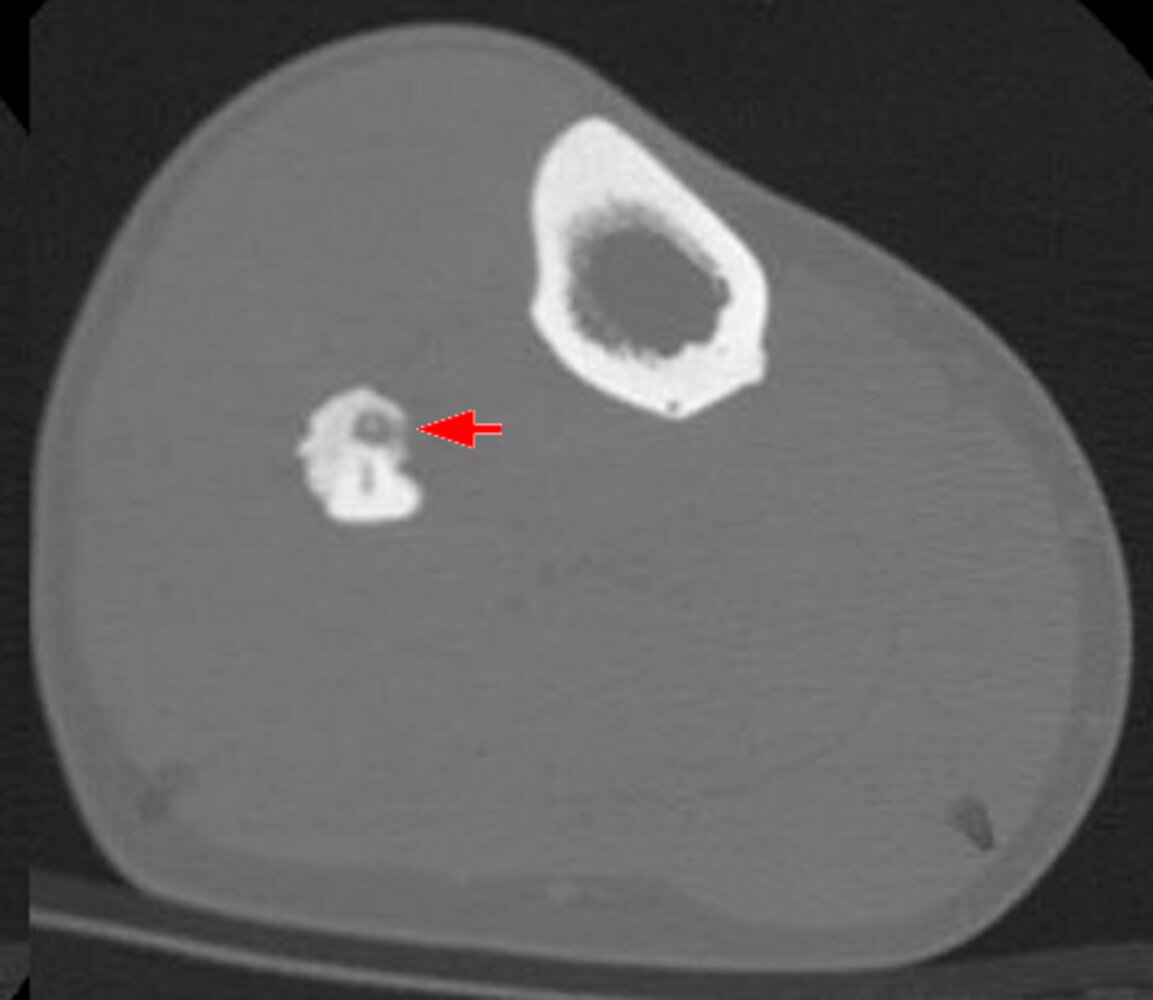

Osteoid osteoma [4]

• Description

• Small tumor (< 2 cm)

• Predominantly located in the cortex of long bones

• Epidemiology

• Peak incidence: 4–25 years [5]

• Sex: ♂ > ♀

• Clinical features

• Located in metaphysis and diaphysis of long bones (predominantly the proximalfemur, tibia, and humerus) and vertebrae

• Constant, intense pain that worsens at night

• Pain is responsive to NSAIDs (e.g., ibuprofen, aspirin)

• Diagnostics

• X-ray or CT: radiolucent core (osteoid), surrounded by perifocal sclerosis (nidus)

• Scintigraphy: usually intense enhancement

• Double-density sign

• Intraoperative nuclear imaging using a probe to detect the tumor

• Treatment: NSAIDs or surgical removal if pain is unresponsive to medical treatment